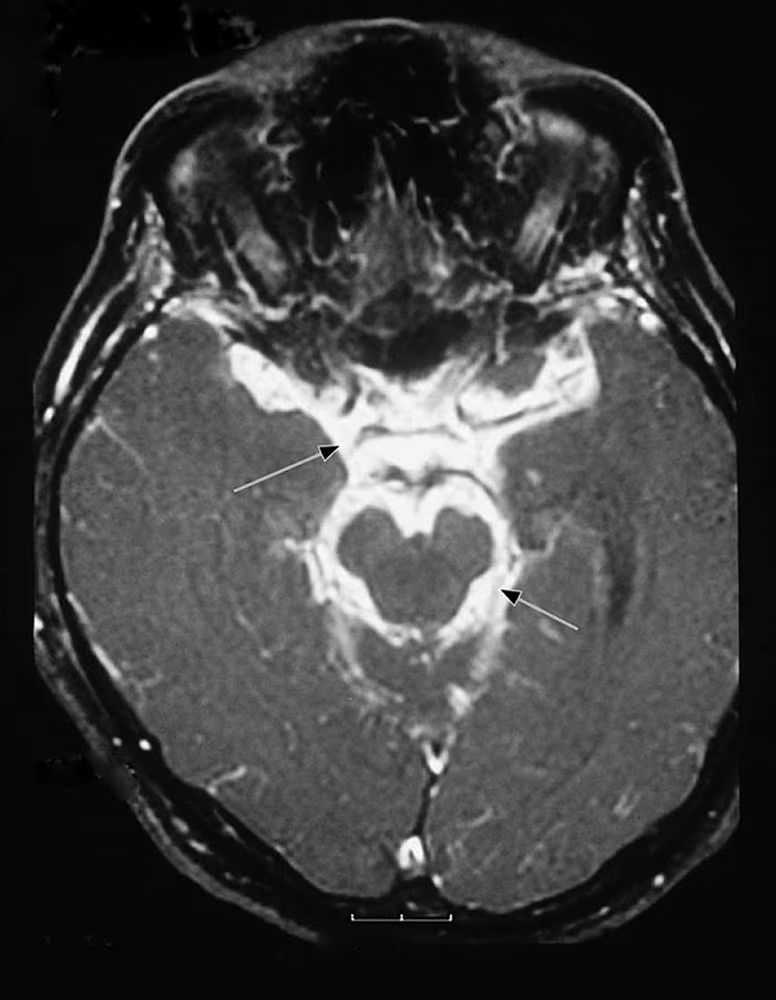

- Компьютерная томография и магнитно-резонансная томография позволяют выявить расширение желудочков головного мозга, гидроцефалию, инфаркты, туберкулемы или туберкулёзные абсцессы, а также утолщение базальных оболочек. При контрастировании отмечается накопление контраста в субарахноидальных цистернах и эпендиме[7][9].